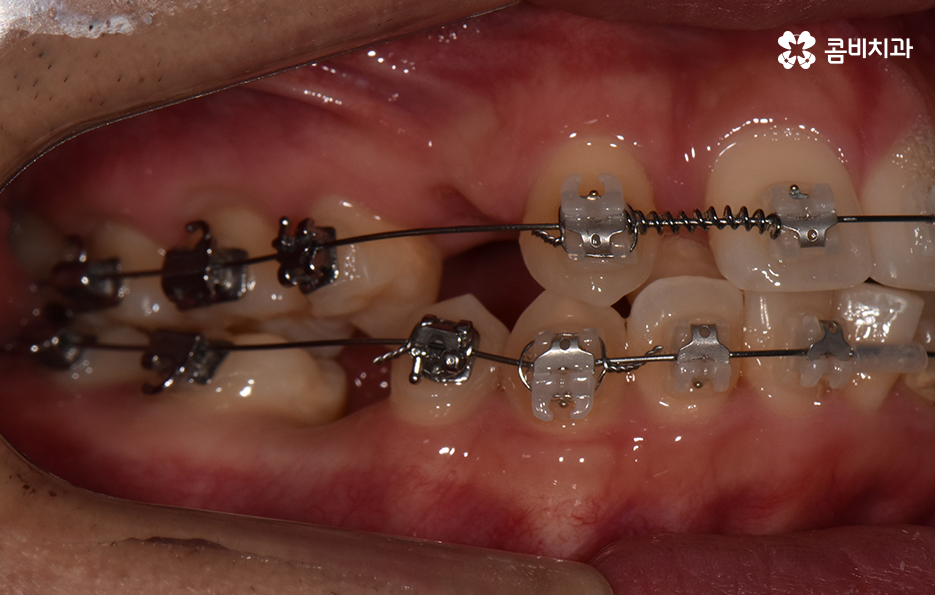

덧니가 나는 원인은 유전적인 영향부터 골격적인 부분 등 다양하지만 기본적으로는 치아가 나올 공간이 부족해서 덧니의 형태로 영구치가 자라는 경우가 많기 때문에 덧니 교정 사례에는 유독 발치 교정 사례가 많이 있는데요

다만 덧니 교정 사례에서 발치교정 사례가 많은 이유는 턱뼈가 좁아서 치아가 덧니로 자란 경우가 많기 때문에 치열을 재배열하기 위해서는 치아가 움직일 수 있는 충분한 이동공간이 필요하기 때문에 공간 확보의 목적으로서 작은 어금니 양옆, 위아래 4개를 발치를 하는 발치교정법이 보편적으로 많이 활용되고 있으며 치아의 이동 공간을 확보하는 방법으로는 발치 교정법 외에도 악궁확장, 어금니 후방이동, 치간삭제와 같은 비발치적인 방법도 가능하기 때문에 치아를 얼마나 이동시켜야 할지에 따라서 치료법은 개인차가 발생되고 있어요

덧니 교정 사례를 살펴보면 치열을 가지런하게 재배열 하는 기준만으로 보면 비발치로도 충분히 교정이 가능한 경우도 많지만 돌출입의 개선이나 입술라인 등을 고려해서 발치교정을 하게 되는 사례도 많이 있어요